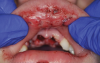

The effects of ENDS on oral mucosa are also not well studied. A pilot study comprised of a small sample of patients examined the prevalence and features of oral lesions among people who had quit smoking (n = 45) compared to e-cig users (n = 45).29 The prevalence of oral mucosal lesions was higher in those who used e-cigs (65.4%) compared to past smokers (34.6%). However, this result was not statistically significant. A case was reported on of a 15-year-old boy who had mouth ulcerations that were suggested to be secondary to marijuana vaping (Figure 3).30 His mouth ulcers disappeared and did not recur after he stopped vaping.

Fig 3. Upper labial mucosa and maxillary vestibular gingiva showing widespread shallow ulceration, erosion, and erythema after use of e-cigs that included marijuana. (Reprinted with permission from Pediatric Dermatology.30 Copyright 2020, John Wiley and Sons)

Figure 3